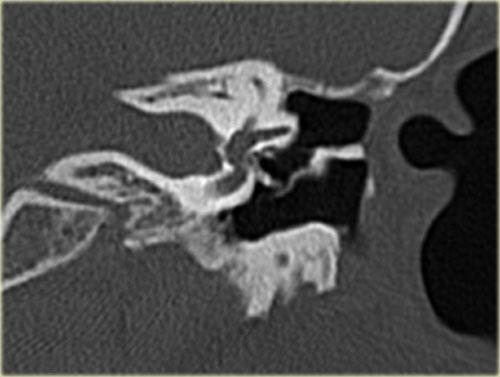

Bên trái là hình ảnh của một phụ nữ 20 tuổi với viêm tai tái phát.

Có mô hạt trên màng nhĩ trái.

CT cho thấy một khối mô mềm nằm giữa chuỗi xương con và thành nhĩ bên, có hình ảnh bị ăn mòn.

Điều này ủng hộ chẩn đoán cholesteatoma.